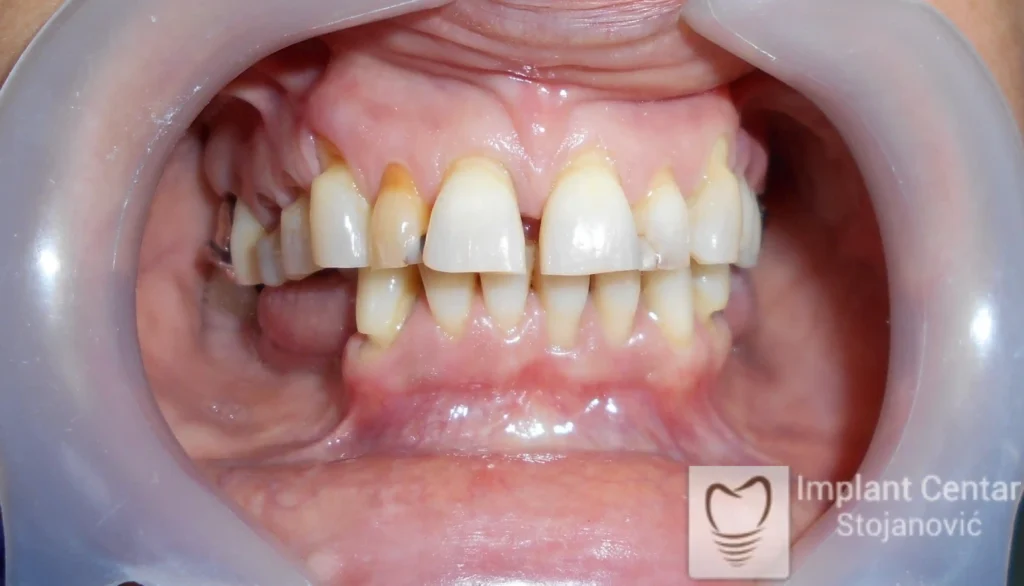

Pacijent sa rascepom usne, nepca i alveolarnog grebena uspešno je rehabilitovan fiksnim protetskim radom na implantatima. Pre dolaska u našu ordinaciju, pacijent je u gornjoj vilici nosio totalnu protezu preko preostalih zuba, dok je u donjoj vilici bio zbrinut parcijalnom mobilnom protezom. Tokom višegodišnje potrage za adekvatnim rešenjem, pacijent nije uspeo da pronađe zadovoljavajuću terapijsku opciju ni u zemlji ni u inostranstvu.

Nakon detaljnog kliničkog pregleda i analize radioloških snimaka, izrađen je sveobuhvatan plan terapije sa ciljem uklanjanja mobilnih proteza i postizanja maksimalne funkcionalne i estetske rehabilitacije. Zbog loše biološke vrednosti preostalih zuba, doneta je odluka o njihovom vađenju i ugradnji dentalnih implantata.

Poseban terapijski izazov predstavljalo je premošćavanje defekta nastalog usled rascepa, kao i ograničena količina raspoložive kosti u gornjoj vilici. Primenom većeg broja implantata i odgovarajućih procedura nadoknade kosti, postignuta je stabilna osnova za fiksni protetski rad.

Tokom perioda oseointegracije, pacijent je bio zbrinut fiksnim privremenim krunicama, čime je već pet dana nakon intervencije obezbeđena potpuna funkcionalna i estetska rehabilitacija. Nakon završetka perioda integracije implantata, izrađeni su definitivni cirkonijum-keramički mostovi na implantatima.

Pacijent je izuzetno zadovoljan postignutim rezultatom, navodeći da po prvi put jasno oseća svoje nepce tokom žvakanja, kao i da se smeje sa punim samopouzdanjem.